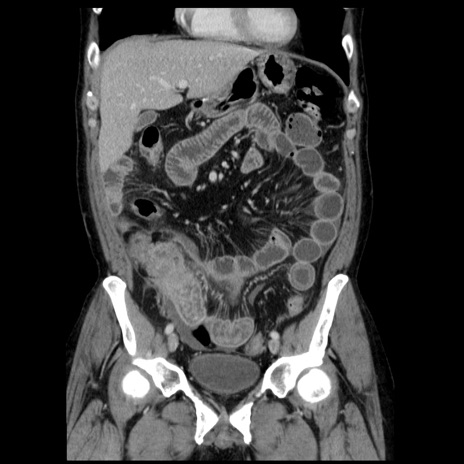

症例29(冠状断像)

【症例】40歳代男性

【現病歴】2日前から胃痛あり。徐々に周期的な激痛に変化した。本日になっても激痛があるため受診。

【身体所見】意識清明、BT 38-39℃台あり、腹部:膨満、やや硬、右下腹部に圧痛あり。

【データ】WBC 8500、CRP 23.26